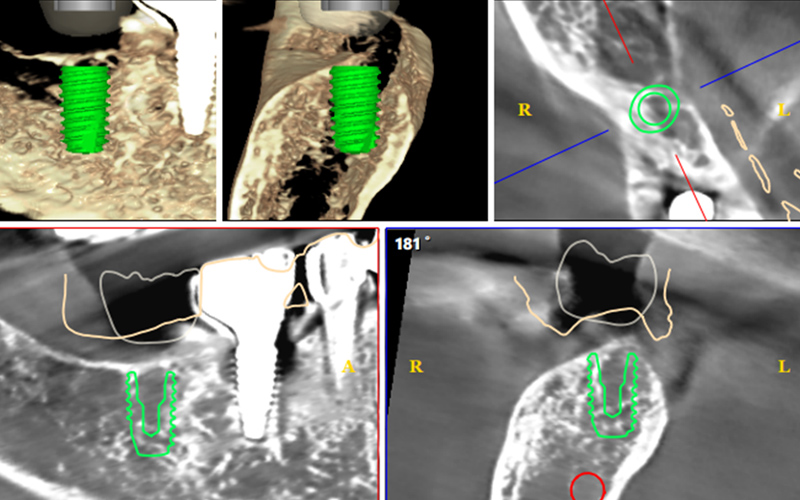

구강 상태와 잇몸 뼈를 정밀하게 진단한 후

개인에게 맞는 계획으로 임플란트를 식립합니다.

얼굴, 골격 관계, 턱관절을 고려한 종합적인 치료계획을 세웁니다.